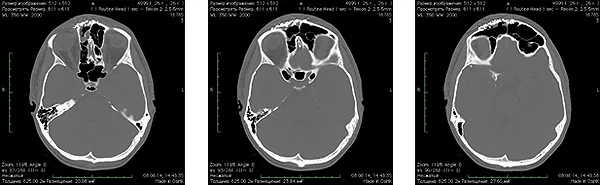

Spiral computed tomography after surgery: